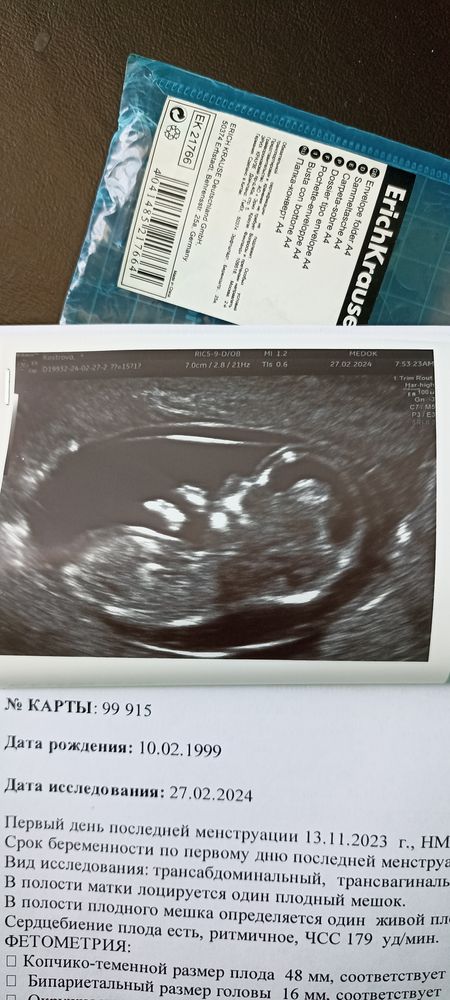

Ох высокий твп . Сделайте прокол - обязательно. Если финансы позволяют можно и Нипт ,но в вашем случае наверное лучше на прокол

Да не только в твп дело - почти на месяц отстаёт КТР плода, отек подкожный...

Kseniya Kostrova, ну это не всегда так,пусть и поздняя,но должно выровняться хоть немного,не в месяц разбег(( обычно пишут фетальный срок ра 2 н меньше,но тут параметры плодика маленькие и КТР особенно